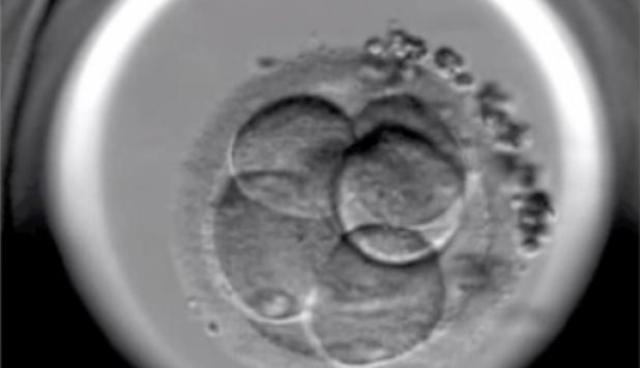

• Los nacimientos in vitro

Los nacimientos in vitro

En 2000 nació el primer bebé "a la carta" libre de la Anemia de Fanconi que padecía su hermana y cuyas células de cordón sirvieron para curarla. La técnica de análisis embrionario (diagnóstico preimplantación tras fecundación in vitro) nos permite evitar el nacimiento de niños con determinadas enfermedades hereditarias.